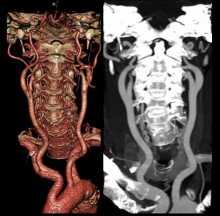

- КТ с введением контрастирующего вещества;

Диагностировать опухолевые образования в позвонках лучше всего с помощью КТ позвоночника или МРТ позвоночника с контрастом.

Диагностику опухолевых заболеваний спинного мозга и позвонков чаще всего проводят при помощи КТ позвоночника или МРТ позвоночника с контрастом. Чтобы выяснить, какой из методов лучше справится с этой задачей, необходимо разобраться в механизме действия каждого из методов.

Компьютерная томография - это рентгенологический вид диагностики. Она дает прекрасную возможность определить новообразование в костных структурах даже на ранних стадиях развития. Однако на КТ визуально сложно разделить патологическую и здоровую ткань в спинном мозге. Для этих целей пациенту проводят процедуру КТ-миелографии с введением контрастного вещества. Использование йодосодержащего контраста не всегда приемлемо. У некоторых пациентов может быть аллергия на состав или серьезная болезнь почек, при которых контраст не применяют. Не стоит забывать и о лучевой нагрузке. В среднем при КТ всего позвоночника пациент получит дозу облучения, равную 5-8 мЗв. Поэтому при диагностике объёмных образований спинного мозга и оболочек приоритетным методом обследования будет МРТ позвоночника с программой миелография.